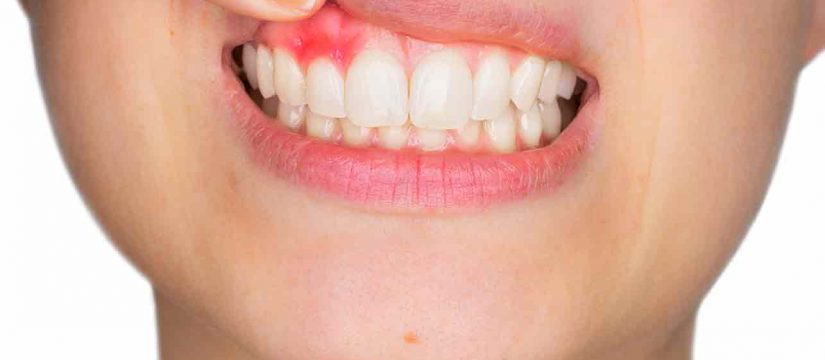

What Causes Uneven Gums?

A number of things can cause your gums to be too low or too high. Gums that cover a large portion of your teeth can make your teeth look small. This may be the result of genetics, a particular health problem, or taking certain prescription drugs. Gums that are too high and make your teeth appear long are often caused by gum recession, a condition in which gum tissue pulls back from a tooth and exposes the tooth's root. Not only can gum recession make your teeth look long, it can lead to serious dental problems such as decay and tooth loss. Gum recession may also be a sign of periodontal disease, the deterioration of the supporting structures of the teeth (gums and bone) . Cosmetic Dentistry:

Gum Contouring Surgery: Is It Necessary?

Gum contouring alone is considered a cosmetic procedure. Most of the time it is not medically necessary. Most people have their gums reshaped to improve the appearance of their smile. However, some people undergo gum contouring surgery as part of other necessary periodontal procedures, such as crown lengthening, pocket reduction, and regenerative procedures.

• Gum contouring procedures not considered cosmetic include adding gum tissue when recession has occurred and trimming overgrown tissue that has covered part of the tooth crown.